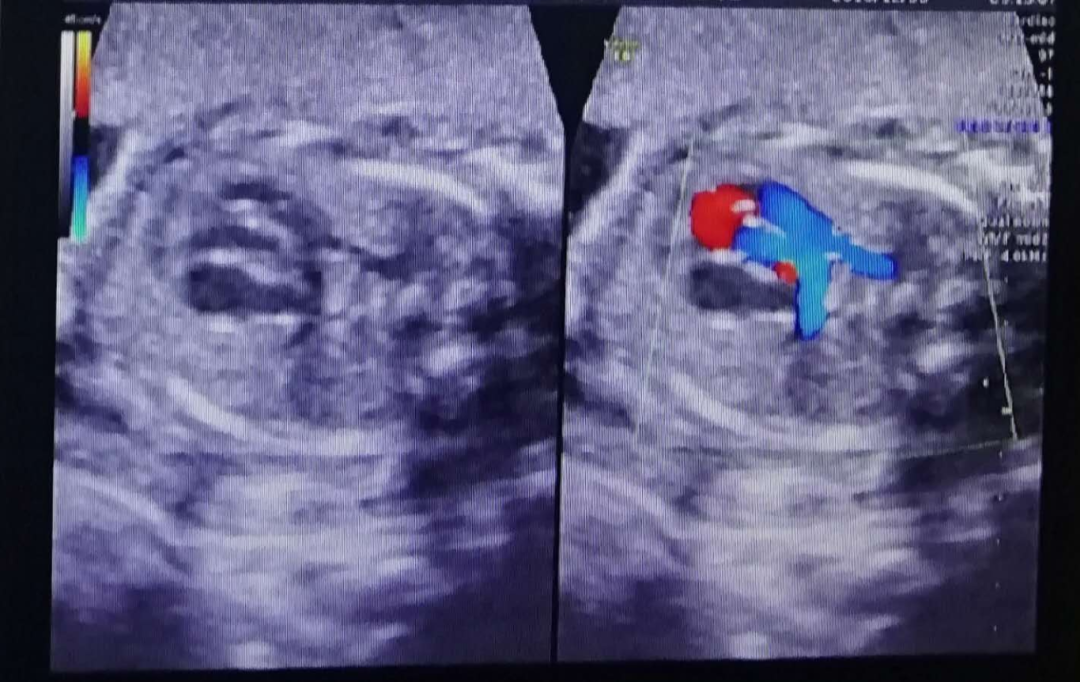

武汉仁爱医院四维大排畸查出复杂新先心...